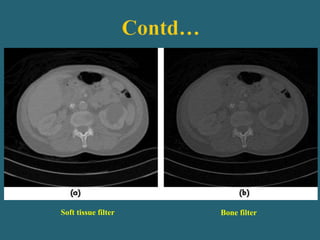

 Mathematical filter applied during reconstruction (filtered back

projection) to remove the blur from images.

 Affects spatial resolution but requires tradeoffs depending on

clinical needs.

 Sharp- high spatial resolution but yields greater image noise.

 Soft or Smooth- Reduces image noise but also degrades spatial

resolution.

Smooth Medium Sharp

Soft tissue filter Bone filter

Reconstruction Filter:- Bone filter produce lower contrast

resolution and soft tissue filter improves contrast resolution